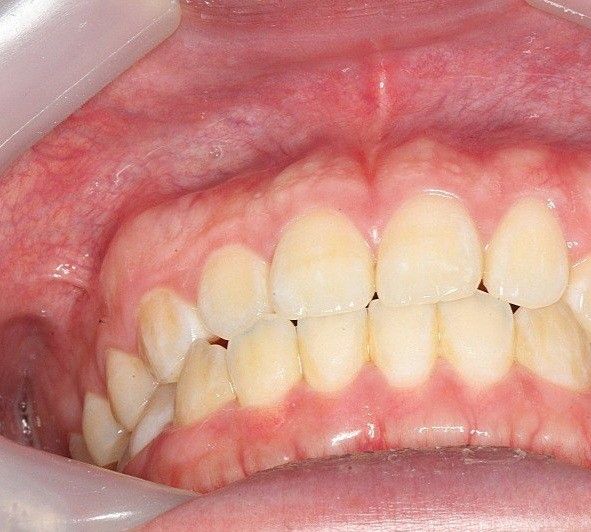

식사를 하거나 일상생활에서 교합을 하는데 큰 문제가 없다면 정상교합으로 판단합니다.

피개량이 적긴하지만 위에 치아가 아래 치아를 덮고 있다면 반대교합이나 절단교합이 아닌 정상교합의 범주에 있다고 판단을 하게 됩니다.